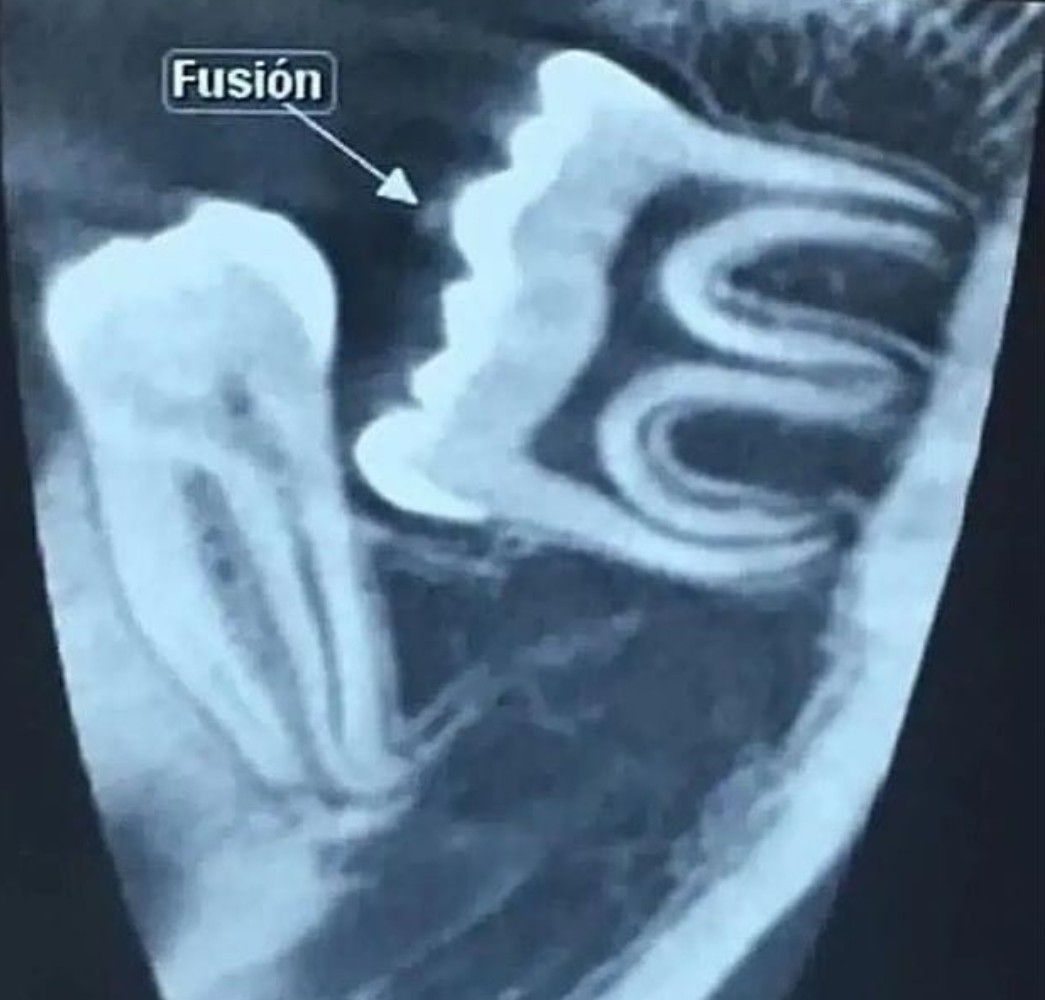

Tooth fusion is defined as the union between two or more separate developing teeth. Such anomaly may be complete or incomplete depending on the developmental stage of the associated tooth buds [1]. If contact between two tooth buds occurs before calcification, complete fusion ensues.